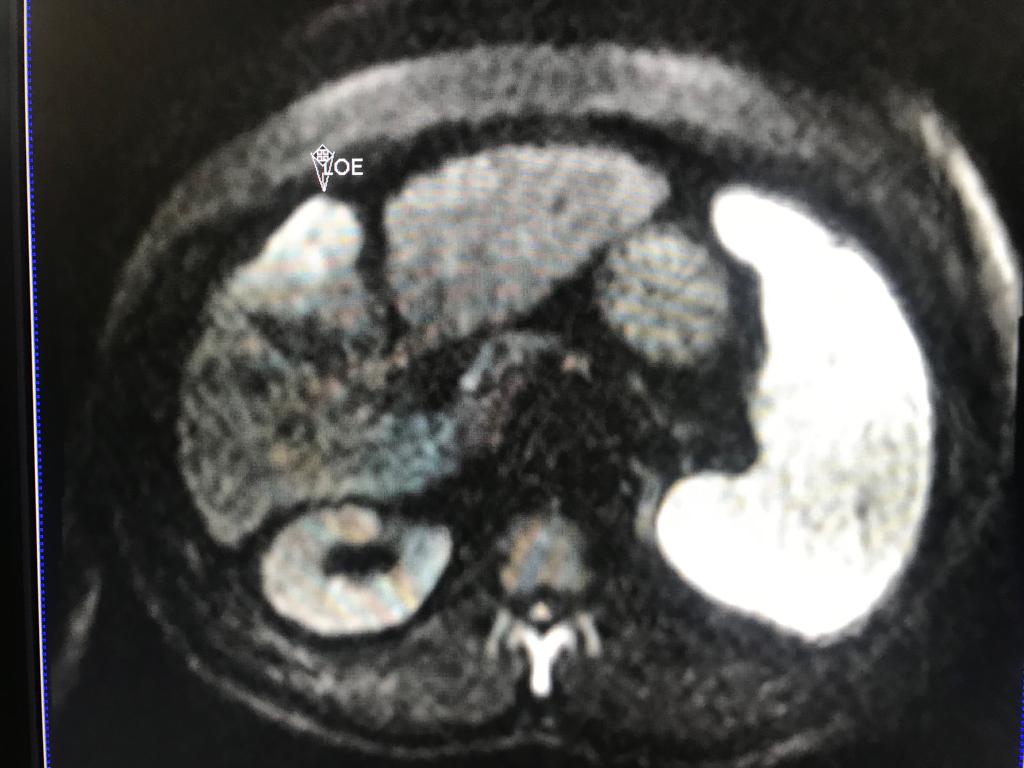

En este contexto, toda nodulación mayor de 1 cm, debe ser evaluada idealmente con RM trifásica con secuencia de Difusión , para discriminar si se trata de nódulos de regeneración , nódulos displásicos o hepatocarcinoma.

En el presente caso, encontramos una lesión típica de hepatocarcinoma en el segmento 5 ( hiperintensa en T2, restringe en la Difusión con ADC bajo. Realza heterogéneamente postcontraste EV, con wash out y presencia cápsula tardía).

El objetivo es identificar dentro de la multifocalidad de nódulos , un hepatocarcinoma precoz o de pequeño tamaño , cuando la posibilidad de tratamiento con intención curativa es viable , a pesar de la cirrosis.